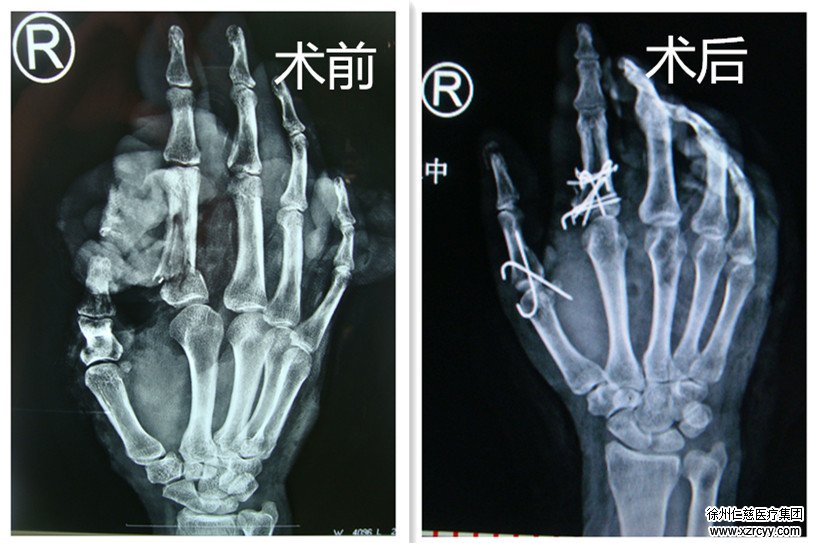

术前术后CT片对比

朱女士的主治医生胡俊生介绍:“病人入院时,右手1-5指脱套性离断,就像脱手套一样,手心手背的皮肉都与骨头分离。我们考虑到再植。”

与普通手术相比,朱女士的再植手术属于撕裂性肢体断离,断离平面不规则、组织损伤严重、有大量异物挤入断面与组织间隙中、易发生感染、常发生血栓形成,是再植手术中难度最高的一种。

整台手术持续6个小时,15日下午一点多才完成。目前朱女士已被转入手外科病房进一步观察。